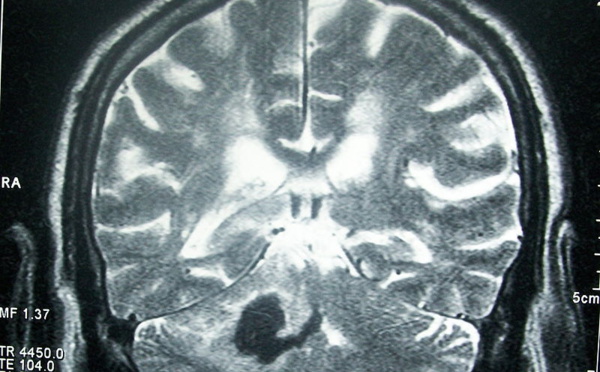

Las conductas impulsivas se corresponden con ciertos patrones de conectividad cerebral - 21/07/2014

Cuanto mayor es el nivel de impulsividad de un niño, mayor es la alteración que este presenta en las conexiones cerebrales de ciertas regiones cerebrales, vinculadas a tareas cognitivas. El hallazgo de estos patrones de conectividad neuronal podría permitir anticipar problemas conductuales. El avance ha sido realizado por científicos de la Universidad de Murcia.